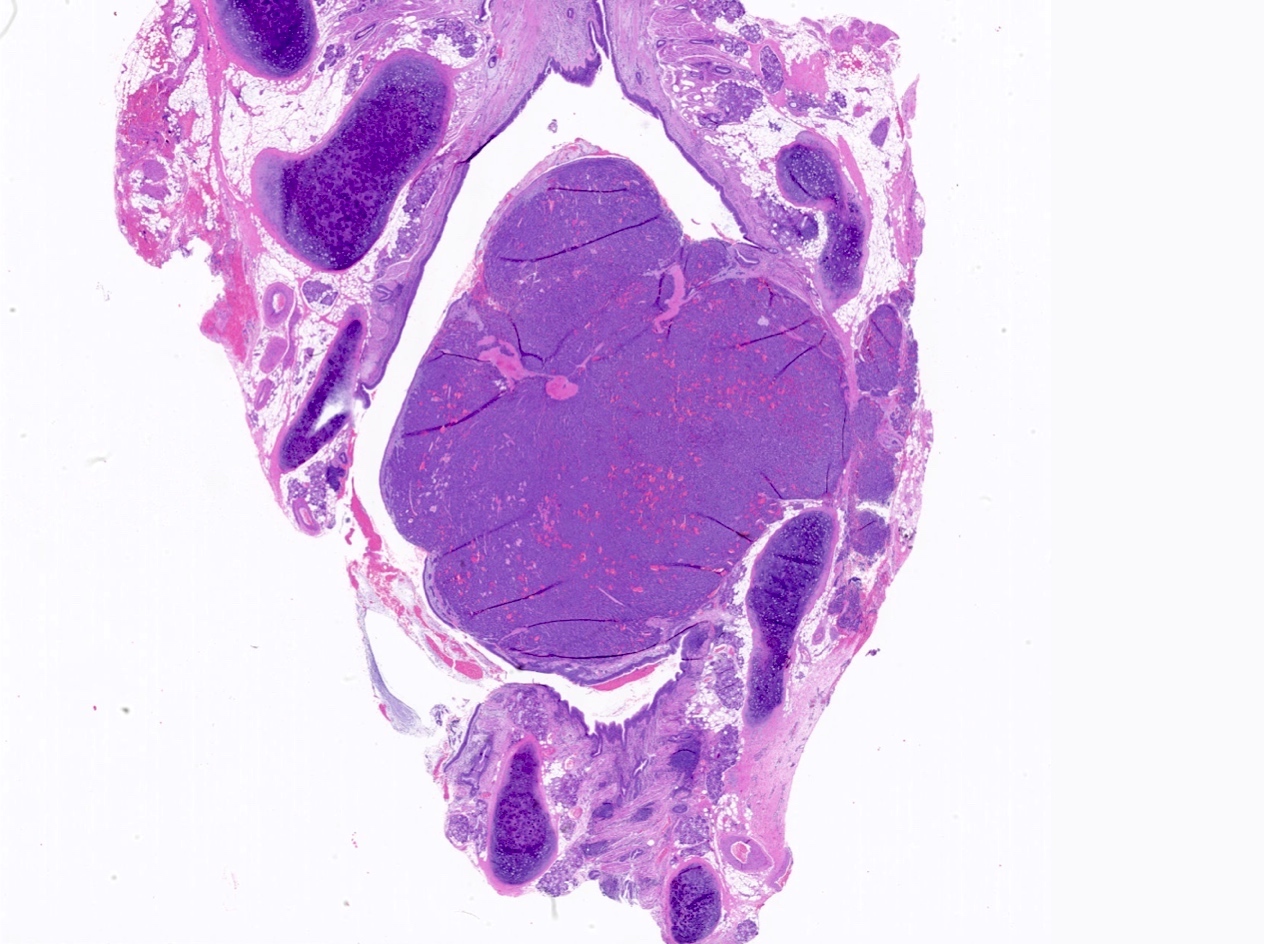

Microscopic (histologic) description

- Diagnostic criteria

- Neuroendocrine tumor with size ≥ 5 mm with < 2 mitoses/2 mm2 and absence of necrosis

- Neuroendocrine growth pattern (organoid, trabecular, rosette formation, nested) or pseudoglandular, follicular and papillary growth

- Tumor cells are uniform with a polygonal shape, round to oval nuclei with salt and pepper chromatin as well as inconspicuous nucleoli and moderate to abundant eosinophilic cytoplasm

- Spindle cells and clear cell features can be seen

- Stroma is fine and highly vascularized; hyalinization, cartilage or bone formation are possible

- Reference: Curr Oncol 2018;25:S86

Microscopic (histologic) images

Contributed by Philippe Joubert, M.D., Ph.D., Jijgee Munkhdelger, M.D., Ph.D. and Andrey Bychkov, M.D., Ph.D.